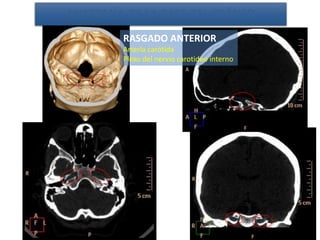

RASGADO ANTERIOR

Arteria carótida

Plexo del nervio carotideo interno

ANATOMÍA DE LA BASE DEL CRÁNEO